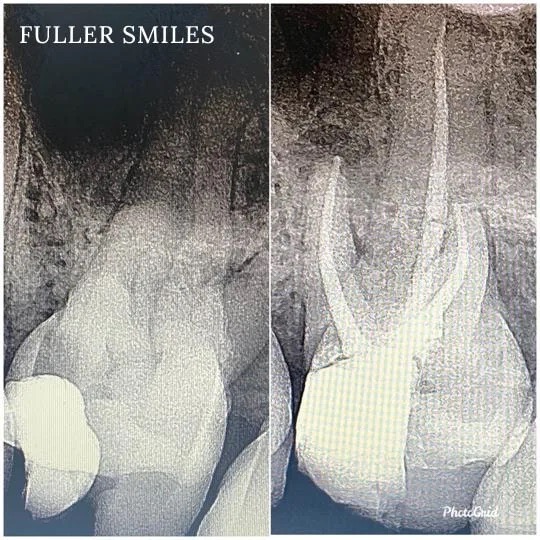

Patient presented to the office with trauma to front two teeth several weeks ago causing her severe pain. After a thorough clinical exam which included endodontic screening and proper x rays led to the diagnosis of necrotic (dead) pulp tissue due to the force of trauma.

Root canals were performed and highly aesthetic Emax crowns were fabricated to meet the patient’s desire to maintain the natural smile and contour as was before the trauma.